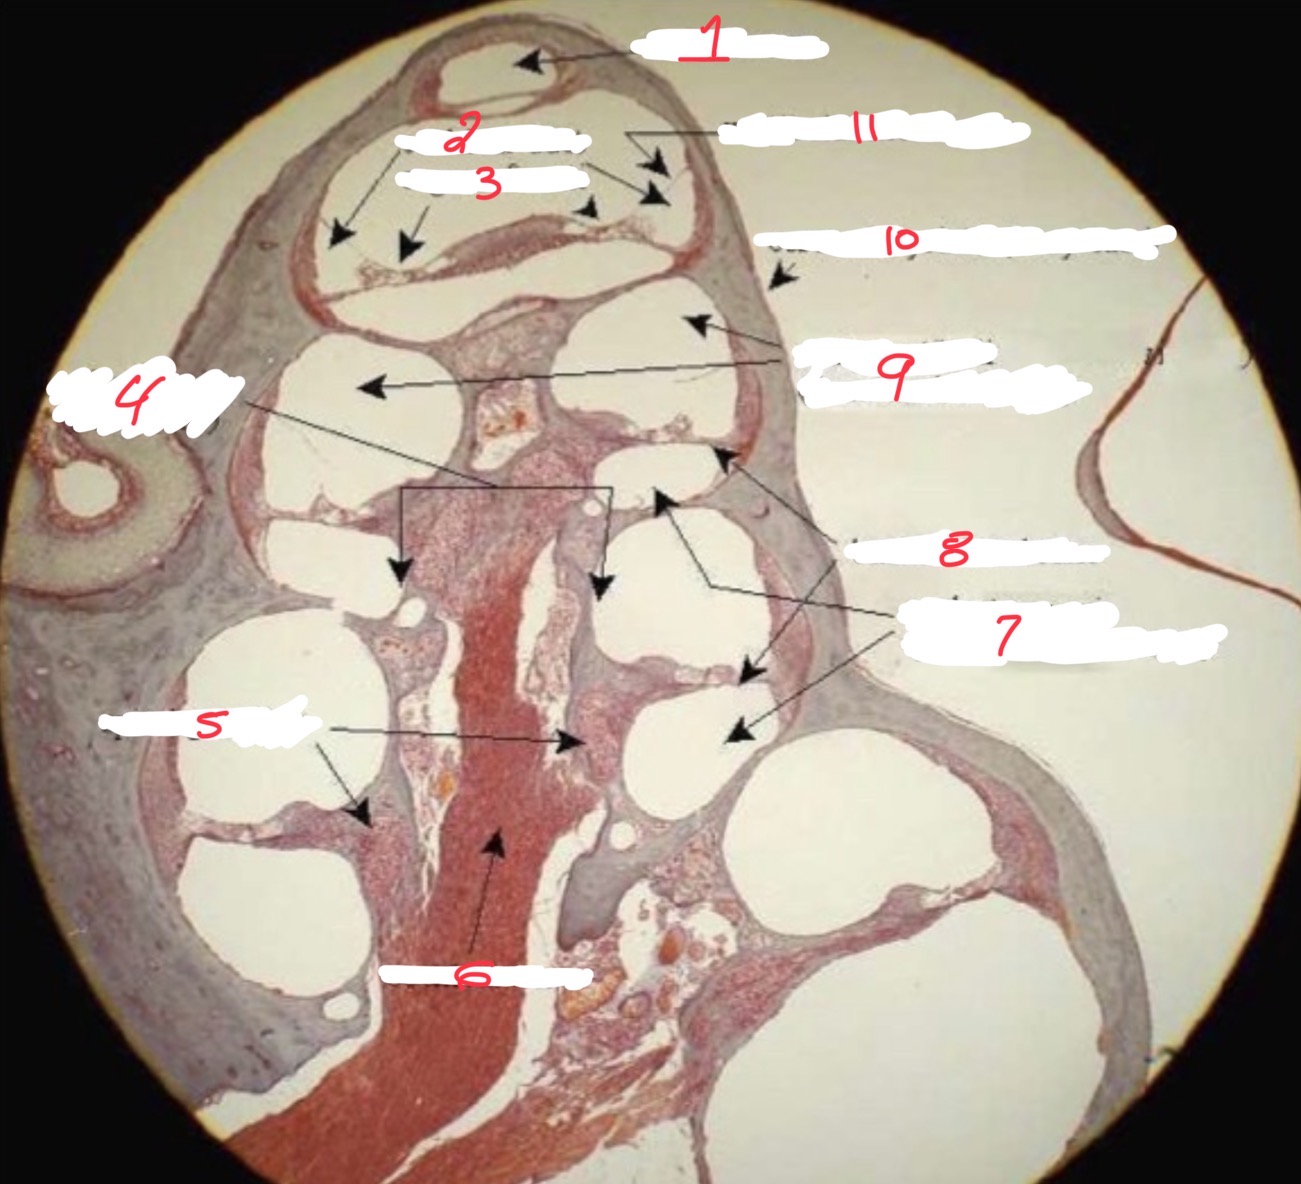

1

pectinate muscle

2

Bicuspid valve

3

Left ventricle

4

Chordae tendineae

5

papillary muscle

6

Trabeculae carneae

Right atrium

pectinate muscles

Aortic semilunar valve